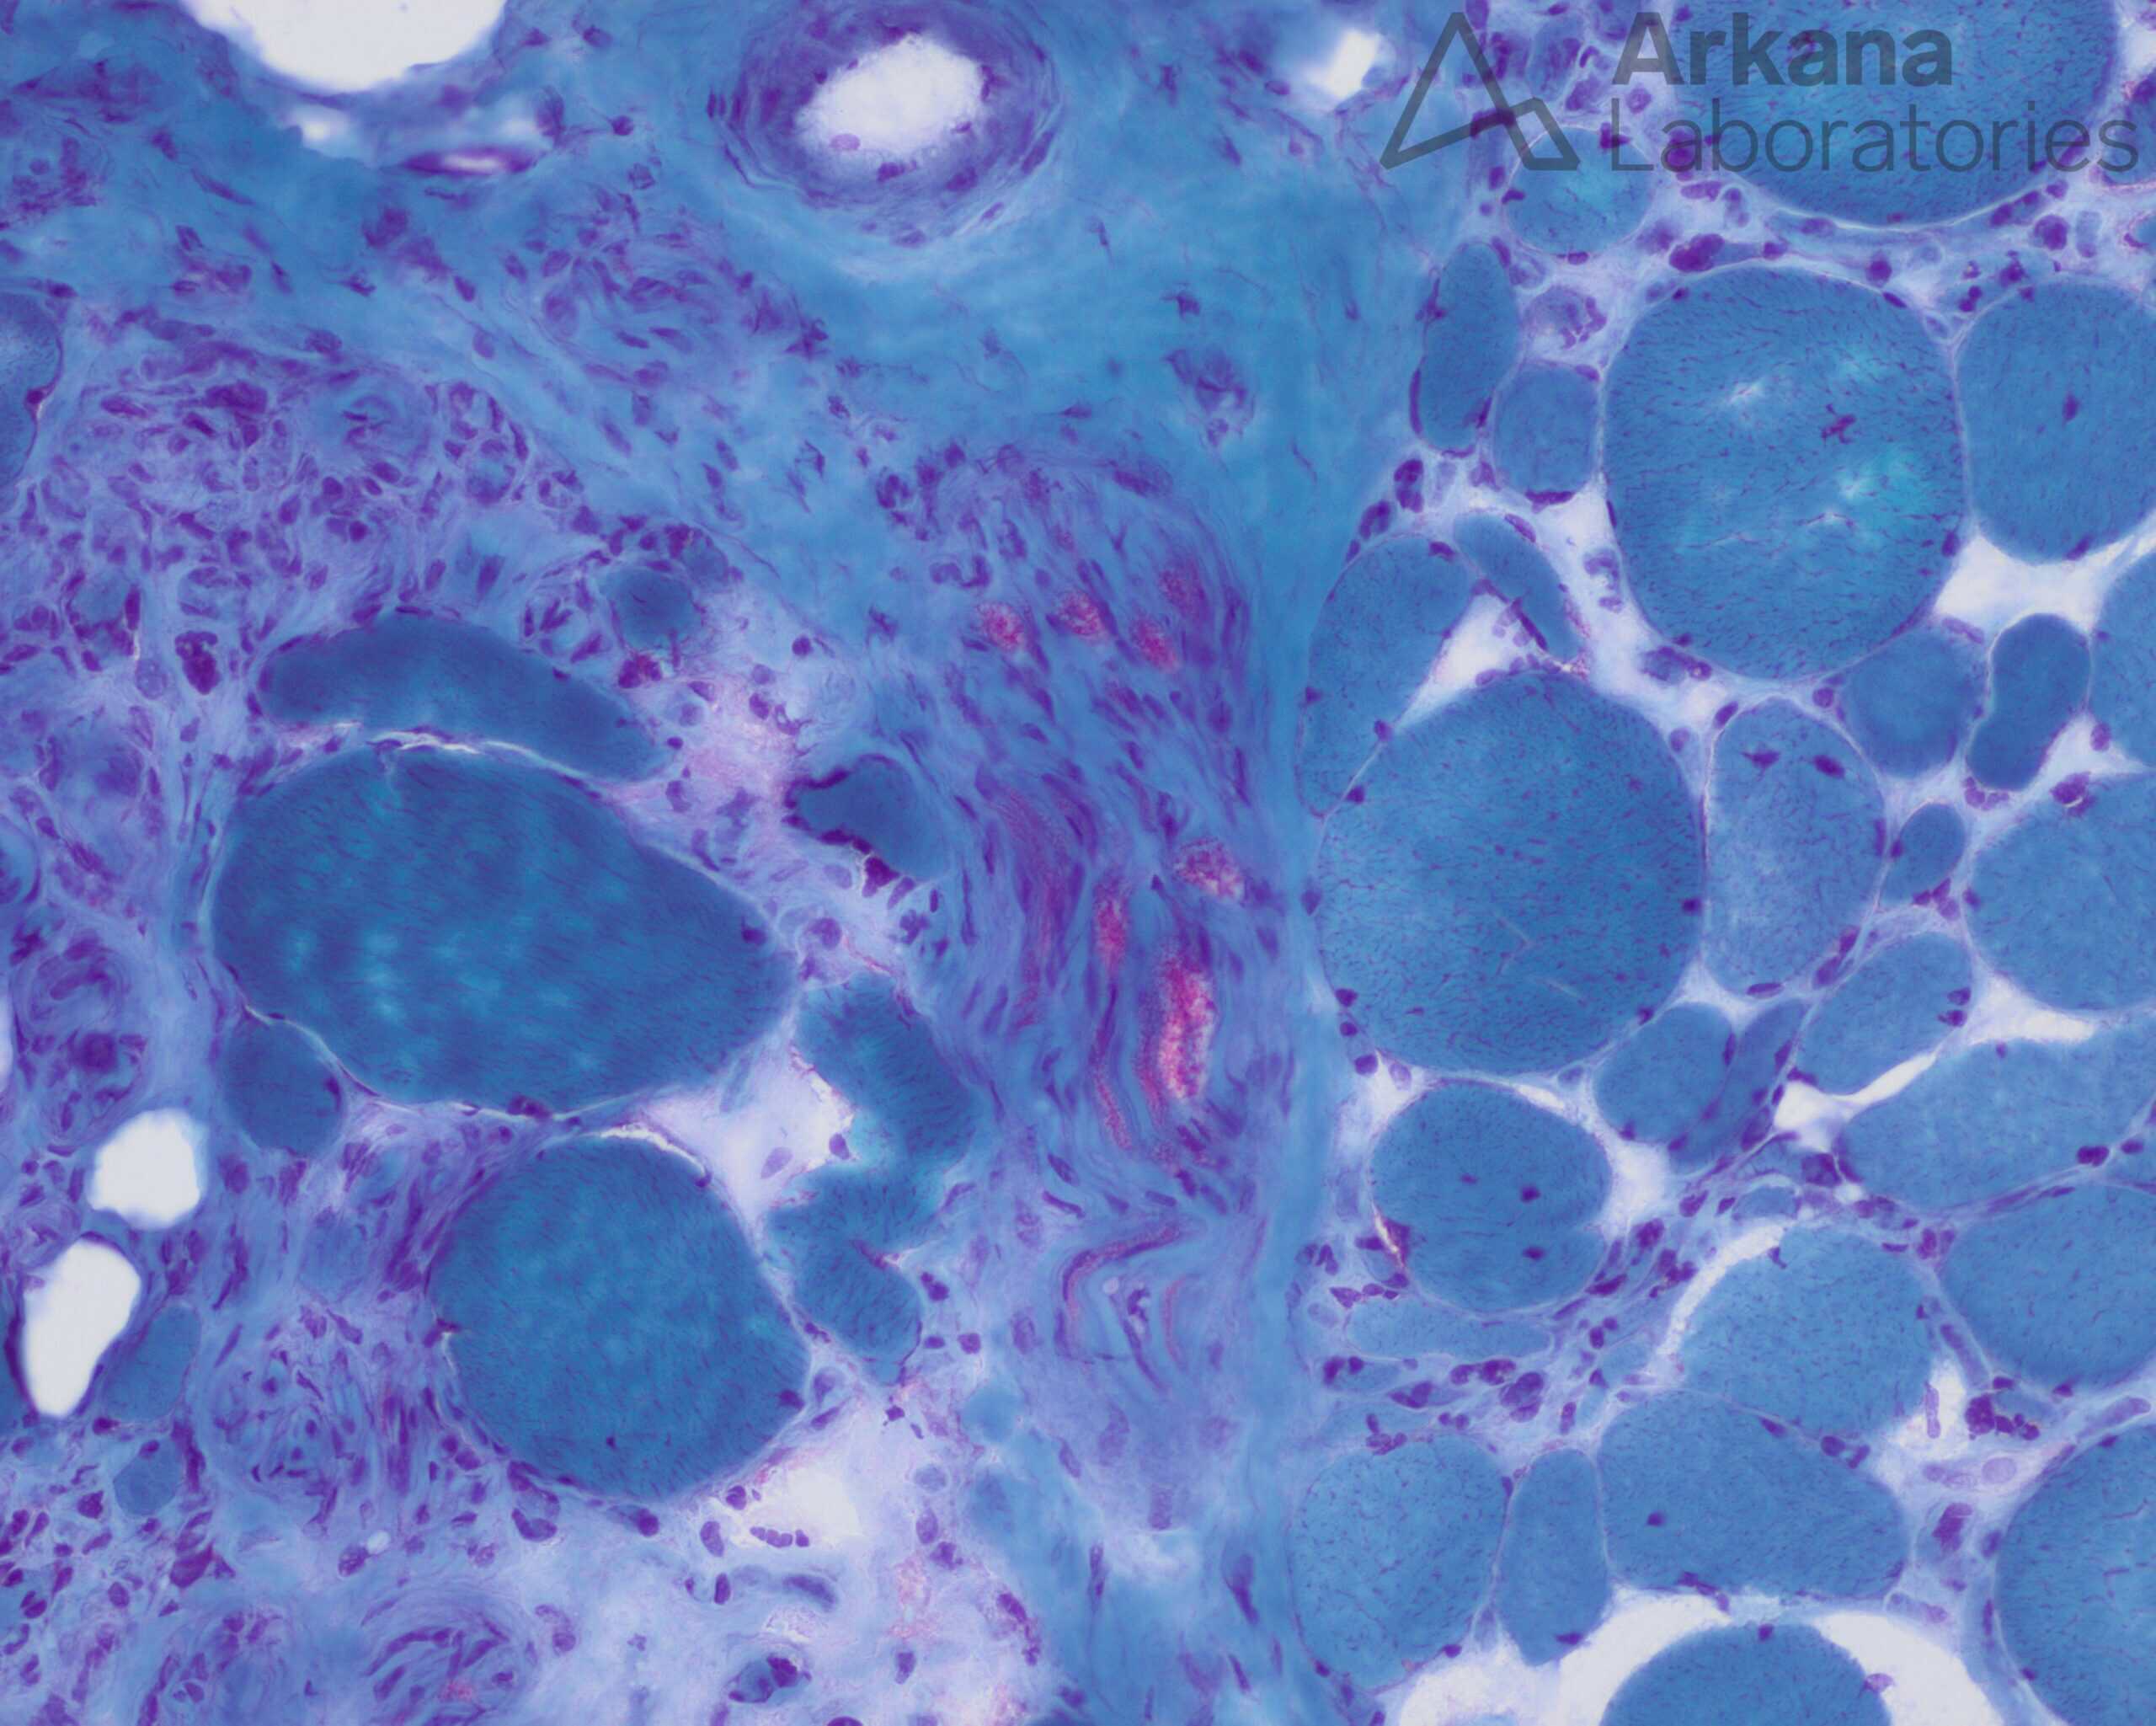

The findings in this muscle that are characteristic for active neurogenic changes are:

- Angulated atrophic fibers that stain darkly on esterase, along with nuclear bags.

- There is also a characteristic “Target” fiber with a light center surrounded by darker staining.

- The trichrome also reveals a peripheral nerve that appears partially depopulated of myelinated axons (red staining).

There is no necrosis, regeneration, fibrosis or internalized nuclei to suggest a myopathic process. Dystrophic muscle would show similar myopathic findings along with marked variation in fiber size and hypertrophic fibers with splitting. An inflammatory processes would most likely be characterized by the presence lymphocytes.